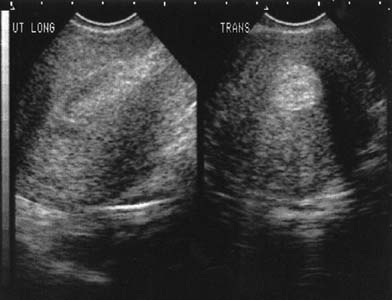

Interestingly, earlier follow-up can be performed if vaginal ultrasonography is used to confirm expulsion. Clinicians must understand what is a normal transvaginal view of the uterine cavity after misoprostol administration, which will contain obvious clot and, sometimes, fluid (Fig. 3). The main goal of the ultrasound examination is solely the determination of the presence or absence of the gestational sac. Harwood and colleagues87 demonstrated that the mean endometrial thickness 24 hours after using misoprostol in women with a complete medical abortion was 17.5 mm but ranged from 7.6 to 29.0 mm. Typically, clinicians define a thickness greater than 15 mm as suspicious for incomplete abortion. One week after the abortion, the mean thickness was 11.3 mm but ranged from 1.6 to 24.9 mm. Fifteen percent of women had an endometrial lining of 16 mm or greater and, traditionally, would be diagnosed as an incomplete abortion. Because all of the women in this trial had a complete abortion, this study points out that it is normal to visualize clot and debris in the uterus when transvaginal ultrasound is used to evaluate a patient after medical abortion. Vaginal bleeding after a medical abortion using mifepristone varies among studies but, surprisingly, the variation is not due to use of different doses of either medication or the route of administration of the misoprostol. Three studies, including two from France, found an average duration of bleeding of 9 days,63,64,75 with a range of 1 to 32 days.63,75 However, the remainder of studies, including those from the United States, report a mean duration of bleeding of 14 to 17 days67,70,76 with a range of 1 to 69 days.65,76,88

Fig. 3. Vaginal ultrasound examination of uterine cavity 1 day after misoprostol administration in a patient receiving methotrexate and misoprostol for abortion.